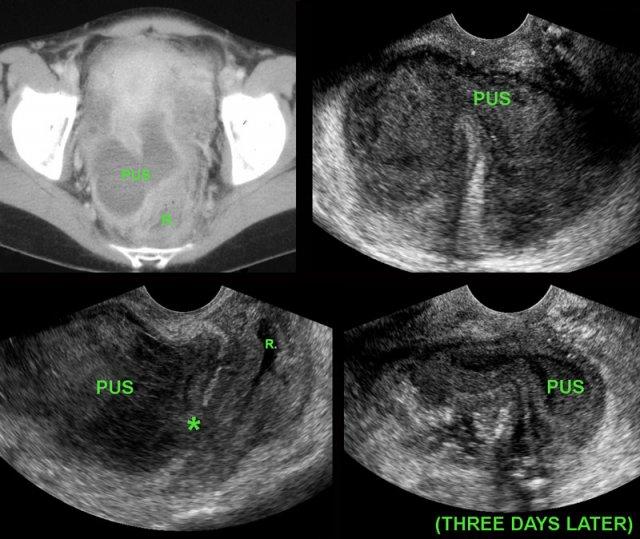

Bệnh nhân nữ trẻ, đau bụng và sốt 10 ngày sau phẫu thuật vì viêm ruột thừa thủng.

CT cho thấy ổ tụ mủ hai thùy, nằm sát thành trực tràng dày, lòng rỗng (R.).

TVUS xác nhận ổ áp-xe và phát hiện một đường hầm giảm âm (*) từ ổ áp-xe thông vào lòng trực tràng (R.), kèm theo xóa mờ khu trú cấu trúc các lớp thành trực tràng đang phù nề.

Những dấu hiệu TVUS này, kết hợp với tình trạng lâm sàng của bệnh nhân đang cải thiện, là dấu hiệu của quá trình tự thoát lưu sắp xảy ra.

Ba ngày sau, ổ áp-xe thành dày gần như đã rỗng hoàn toàn.

Bệnh nhân hồi phục mà không cần dẫn lưu bằng phẫu thuật hay can thiệp dưới hướng dẫn hình ảnh.